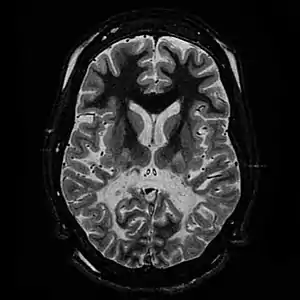

| White matter, with reduced volume and increased signal intensity. The anterior white matter is spared. Features are consistent with X-linked adrenoleukodystrophy. | |

The Loes score is a rating of the severity of abnormalities in the brain found on MRI. It ranges from 0 to 34, based on a point system derived from the location and extent of disease and the presence of atrophy in the brain, either localized to specific points or generally throughout the brain. A Loes score of 0.5 or less is classified as normal, while a Loes score of 14 or greater is considered severe. It was developed by neuroradiologist Daniel J. Loes MD and is an important tool in assessing disease progression and the effectiveness of therapy.[12]